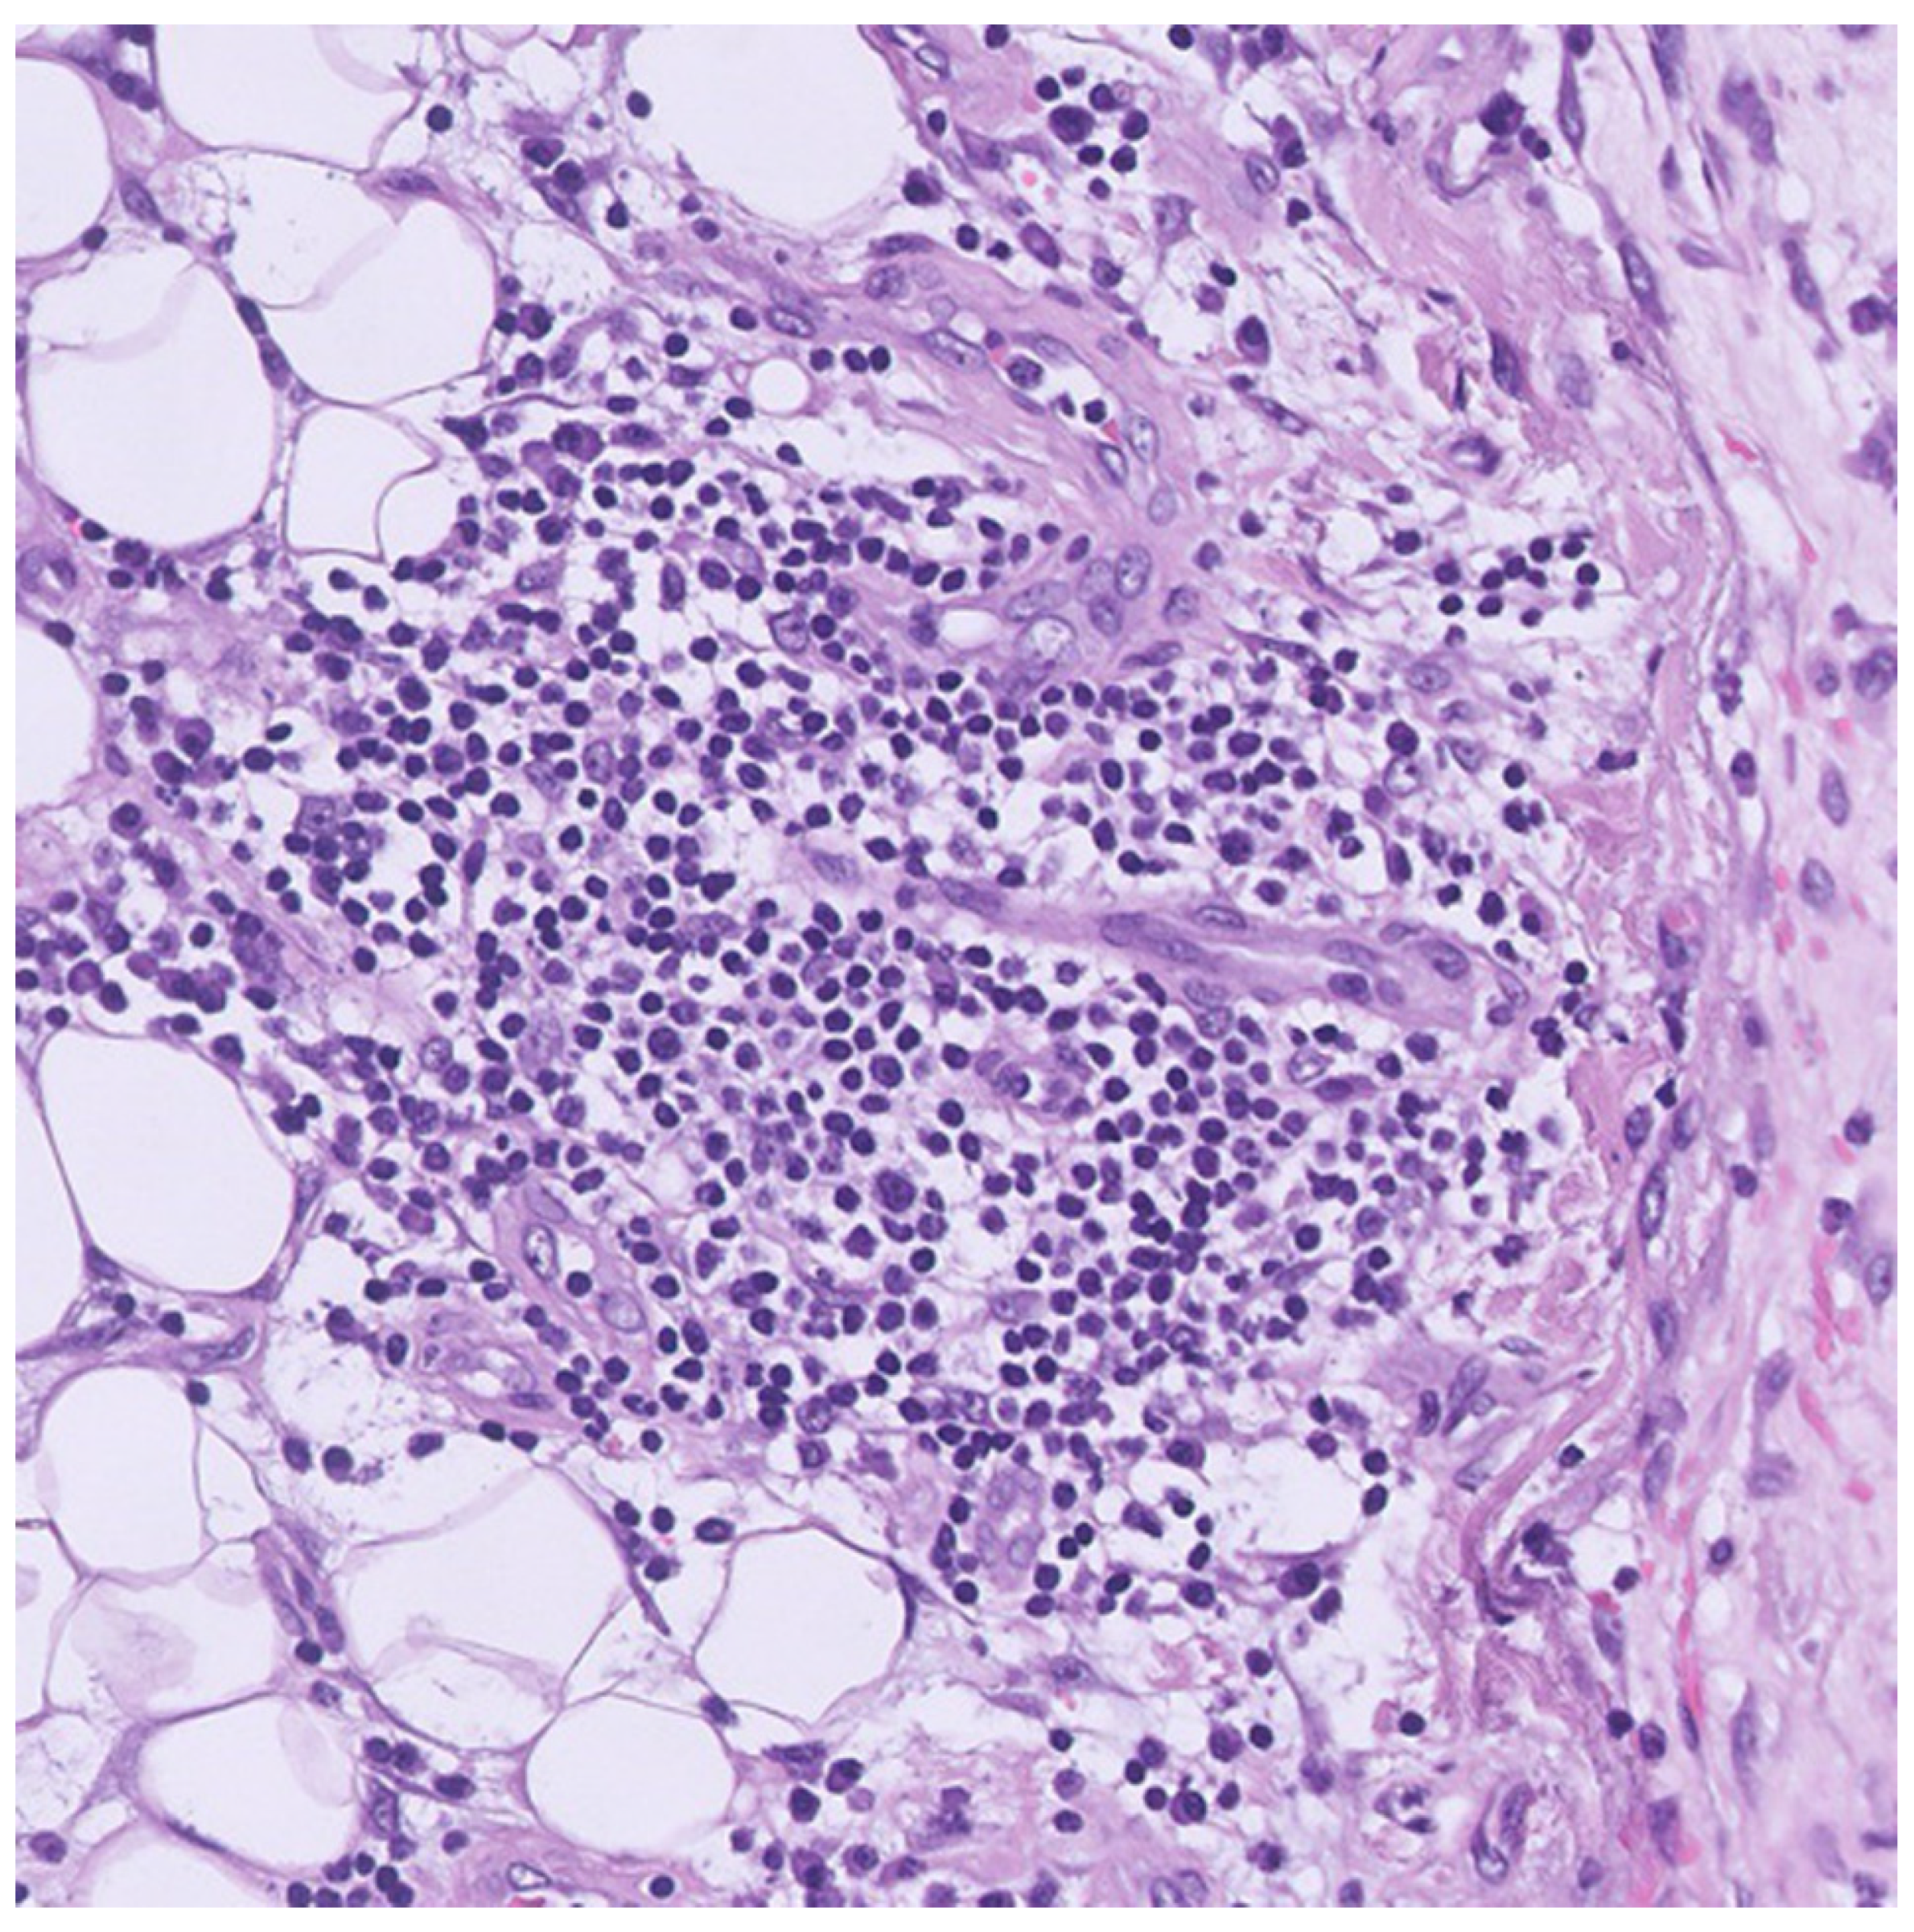

2. Case Presentation